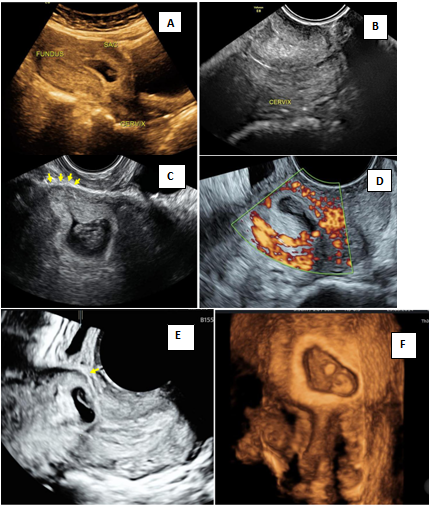

Figure 4 is an illustration of caesarean scar pregnancy with echogenic trophoblastic tissue implanted in the scar site with anterior myometrial thinning and peritrophoblastic flow. Figure 5 is 3D illustration showing ballooning of the cervico-isthmic region and normal appearing cervix (compare with Figure 2D of CP). Multiplanar imaging showing deficient anterior myometrium at the uterovesical interface (Figure 5C & 5d).

Figure 4 Caesarean scar pregnancy (CSP).

A) Lowlying gestational sac seen on transabdominal image B) Empty cervical canal in transvaginal examination C) Transvaginal image showing echogenic trophoblastic tissue in the scar site with anterior myometrial thinning (arrow) D) Peritrophoblastic flow on doppler E) 3D image showing anterior myometrial thinning (arrow) F) Rendered image showing empty cervical canal and sac implanted at scar site.

Figure 5 3D imaging in Caesarean scar pregnancy (CSP).

A) Peritrophoblastic flow B) Surface rendering mode of cervix and sac in CSP C&D) multiplanar imaging of gestational sac showing live embryo and yolk sac, sac implanted at the scar site with deficient anterior myometrium at bladder-uterine serosal interface (arrow).